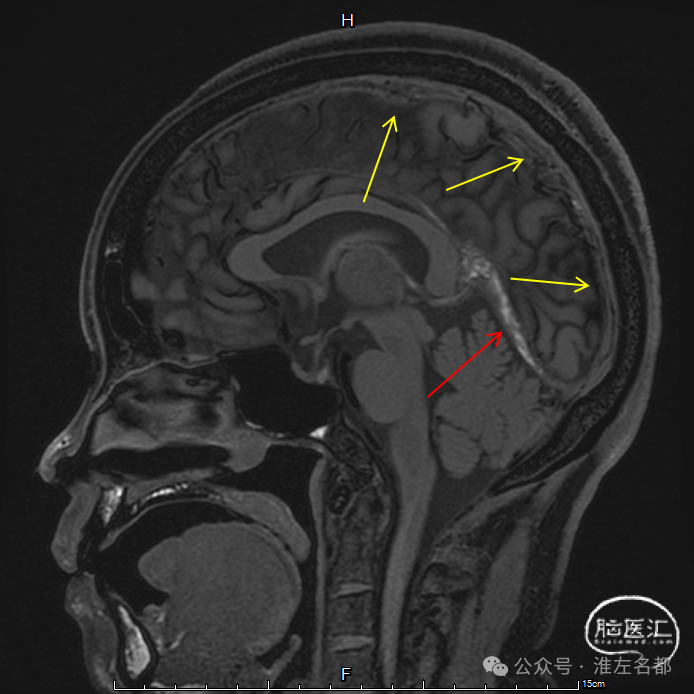

增强MRV:左侧横窦-乙状窦显影纤细;上矢状窦和右侧横窦-乙状窦充盈缺损;脑深部静脉和直窦未见显影。

SWI:双侧丘脑渗血改变,右侧基底静脉和大脑中静脉血栓。

三维黑血高分辨T1

三维黑血高分辨T1平扫(上图)和增强(下图):右侧乙状窦慢性血栓,平扫呈等低信号,并显著强化。

三维黑血高分辨T1平扫(上图)和增强(下图):右侧横窦慢性血栓。

三维黑血高分辨T1平扫(上图)和增强(下图):上矢状窦慢性血栓;直窦内新进血栓(急性血栓等低信号,或亚急性血栓高信号,无强化)。

三维黑血高分辨T1平扫(上图)和增强(下图):左侧横窦发育细小。

三维黑血高分辨T1平扫(上图)和增强(下图):左侧乙状窦局部未发育。